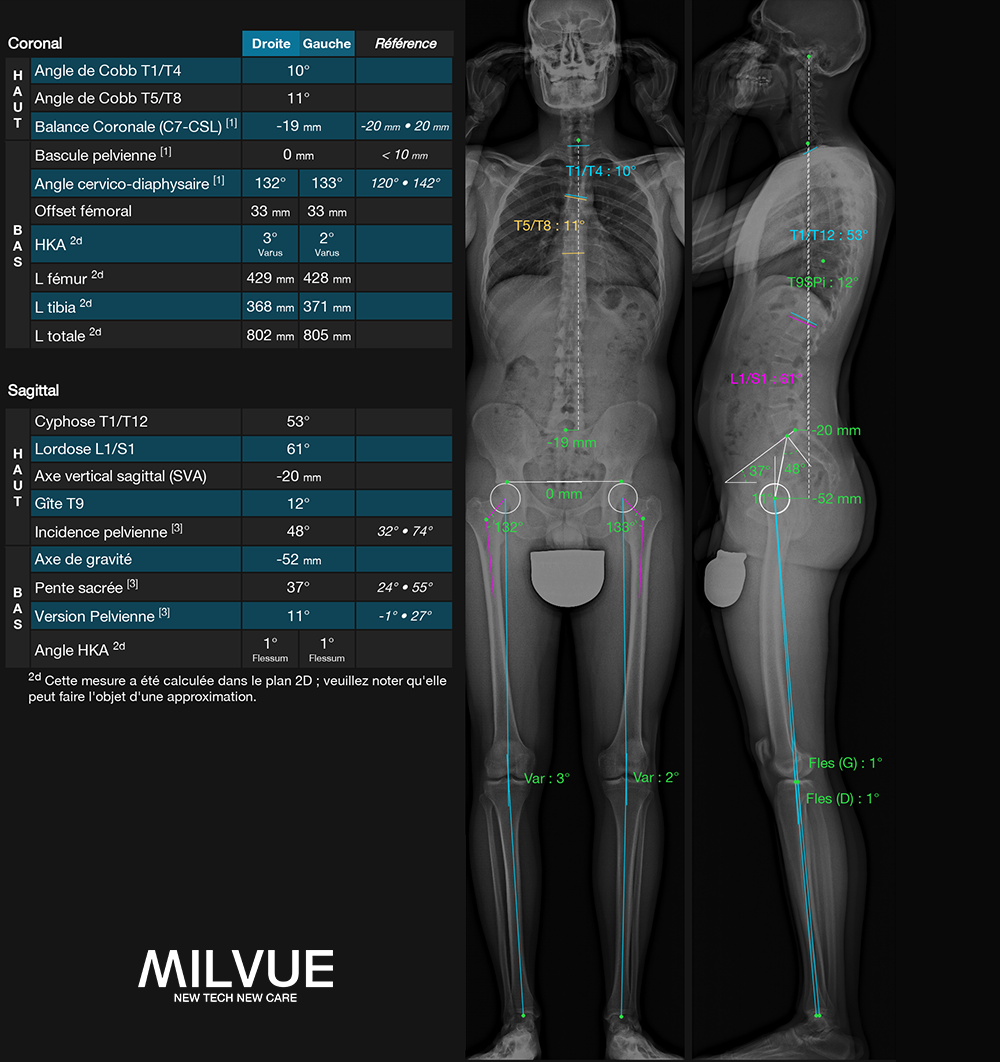

EOS-compatible measurements, with analysis report

TechCare Spine addresses the unique challenge of spinal medical imaging. The spine has significant anatomical complexity, and its central role in body posture and mobility must be leveraged by the latest deep learning advancements. This is why we provide radiologists and orthopedic surgeons with TechCare Spine, a tool for automatic measurements adapted to EOS imaging, offering significant time and productivity savings.

PELVIS : Pelvic version | Pelvic incidence | Sacral slope

SPINE : Coronal balance (CVA) | Sagittal balance (SVA) | Cyphosis T1-T12 | Heel T9 | Lordosis L1/S2 | Cobb angle | Gravity axis

INTUITIVES OUTPUTS showing frontal and profile views together